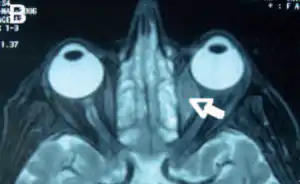

Orbital lymphoma

Orbital lymphoma is a common type of non-Hodgkin lymphoma that occurs near or on the eye. Common symptoms include decreased vision and uveitis. Orbital lymphoma can be diagnosed via a biopsy of the eye and is usually treated with radiotherapy or in combination with chemotherapy.